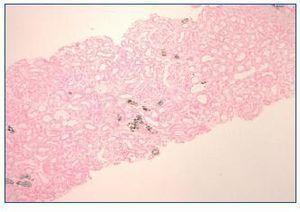

A week later, the patient reported pedal and orbital oedema and was observed on the emergency department. The physical examination was unremarkable except for hypertension (180/80 mmHg) and lower limbs oedema. Laboratory results showed haemoglobin 11.1 g/dl, serum urea 346 mg/dl, serum creatinine 9.2 mg/dl, serum sodium 130 mEq/L, serum potassium 6.5 mEq/L, serum phosphorus 6.6 mg/dl, normal serum calcium, serum bicarbonate 15 mEq/L and mild proteinuria. Serum and urine immunoelectrophoresis and immunologic study were normal. Renal ultrasound showed increased cortical echogenicity. Haemodialysis was initiated. Kidney biopsy showed minimal mesangial expansion. The tubules were mildly dilated and focal interstitial fibrosis was present. Von Kossa stain positive deposits were observed within the cytoplasm of tubular epithelial cells, tubular lumen and interstitium (figure 1 and figure 2). Immunofluorescence was negative for immunoglobulin or complement.

The second form is due to AphN with a more insidious onset (days to months) and is generally irreversible1. At the time of diagnosis, serum phosphorus and calcium levels are normal, unless measured within 3 days of bowel preparation. This was in fact the case of the first patient. As we found, the main pathologic finding in kidney biopsy is nephrocalcinosis demonstrated with the Von Kossa stain1.

Figure 1. Kidney biopsy. Von Kossa coloration (40x).